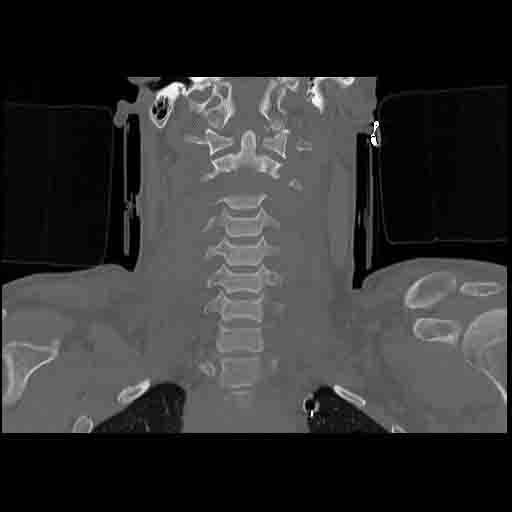

NEWCASTLE – Tony Cowan, 29 anni, è riuscito a sopravvivere, contro ogni pronostico medico, dopo che la testa è stata recisa dalla colonna vertebrale in un brutto incidente.

I tessuti muscolari hanno evitato che si staccasse dal collo dopo che la sua auto subì un brusco impatto dopo averne perso il controllo. Secondo quanto riporta Metro.co.uk, Tony, un ex muratore è riuscito a sopravvivere ma oggi è costretto a stare su una sedia a rotelle e a comunicare attraverso una macchina.

La sua compagna e la sua famiglia erano convinti che sarebbe morto, ma è riuscito a sopravvivere. Tony Cowan comunica grazie a una particolare macchina che emette segnali luminosi, non cammina e ha bisogno di aiuto per svolgere ogni minima azione quotidiana.